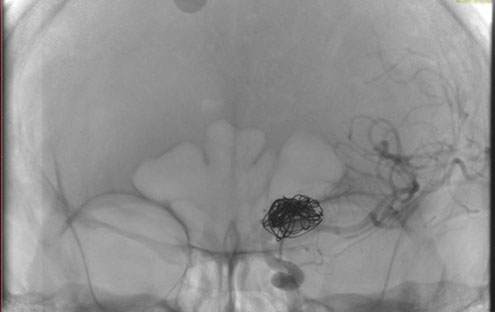

La paciente ingreso al Servicio de Hemodinamia el día martes 11 de febrero con un aneurisma cerebral gigante en la carótida izquierda y se le practicó una embolización; es decir una oclusión por dentro del mismo, donde se colocó un dispositivo denominado coils más un stent diversor de flujo. El procedimiento fue exitoso y contó con la colaboración de médicos neurointervencionistas del Instituto Oulton de la Ciudad de Córdoba.

La paciente llevaba un tiempo refiriendo dolores de cabeza, trastornos visuales por lo cual luego de realizarcele los estudios pertinentes y comprobar la patología se programó el procedimiento. Debido a que el Hospital Vera Barros no contaba con la tecnología necesaria para esta práctica compleja es que se realizó en la nueva Sala de Hemodinamia de INCOR en el marco de un convenio de trabajo conjunto entre la salud pública y la privada.